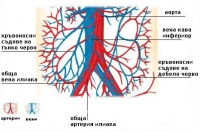

S35.4 Травма на бъбречните кръвоносни съдове

Травма на бъбречните кръвоносни съдове обхваща 16% от всички коремни съдови наранявания. 1,3 - 1,6 п...